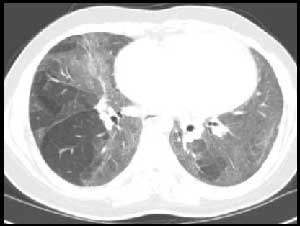

风湿性疾病肺受累常见影像学表现

非特异性

普通

急性间质性

淋巴细胞间质性

脱屑性

COP

类风湿结节